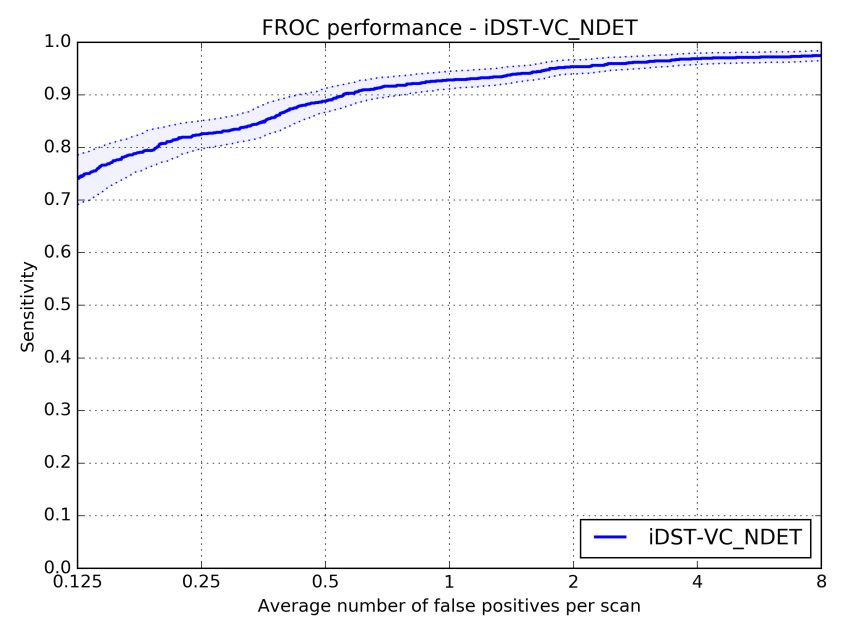

2017 年 7 月,国际权威肺结节检测大赛 LUNA16 要求选手对 888 份肺部 CT 样本进行分析,寻找其中的肺结节。样本共包含 1186 个肺结节,75% 以上为小于 10mm 的小结节。最终,阿里云 ET 在 7 个不同误报率下发现的肺结节平均召回率达到 89.7%。(召回率指在样本数据中成功发现的结节占比,下图显示了 ET 在不同误报次数下的召回率情况。)

(FROC曲线)

其背后的技术由阿里巴巴 iDST视觉计算团队完成,负责人华先胜介绍,与常用的两阶段检测方法不同,他们创新性地使用了单阶段方法,全程无须人工干预。机器全自动读取病人的 CT 序列,直接输出检测到的肺结节。在模型结构设计上,ET 针对 CT 切片的特性,采用多通道、异构三维卷积融合算法、有效地利用多异构模型的互补性来处理和检测在不同形态上的肺结节 CT 序列,提高了对不同尺度肺结节的敏感性;同时使用了带有反卷积结构的网络和多任务学习的训练策略,提高了检测的准确度。比赛中,团队克服了一系列挑战:如结节模态复杂问题,早期的结节小(小于10mm),传统的机器学习和用于自然图像的深度学习网络通常难以凑效。